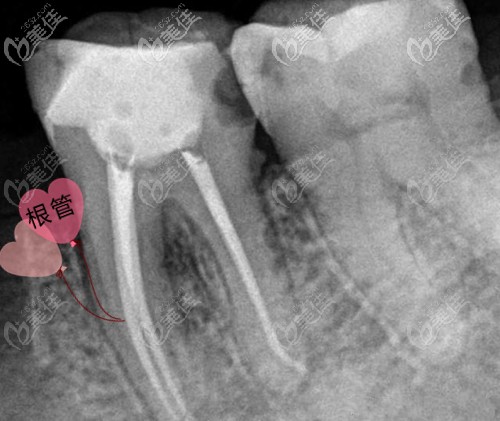

你好,二次根管治疗确实比初次治疗麻烦很多,也确实收费更高,而且根管再治疗以后牙体组织可能被破坏的比较多,剩余量更少,还有就是根管比原来可能要更加的粗大,受力的时候就更容易导致牙折、根裂,做完后建议使用全瓷冠修复。

前牙相对而言根管系统简单一些,一般只有一个根管(牙神经管),而后牙根管系统就复杂多了,有3个、4个或者5个,而且后牙的根管也比较细小,更加不易治疗。那收费自然也就比前牙贵了。

大致来说,一颗牙根管再治疗的费用在1000元~1800元左右。与存在残髓、遗漏根管或根充不完善等有关。建议在有显微镜的牙科治疗,以确保疗效。